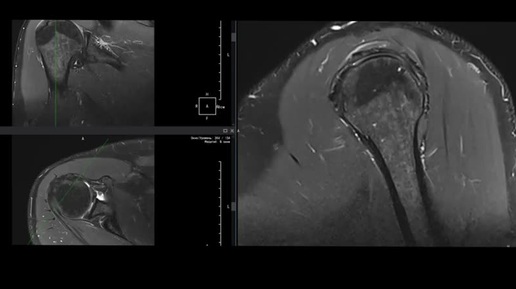

МРТ плечевого сустава